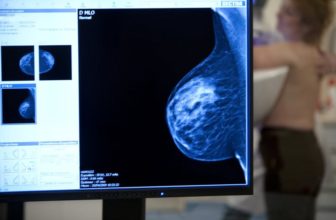

يتم استخدام نفس التقنيات المستخدمة لتشخيص سرطان الثدي لدى النساء عند الرجال، وهي:

• التصوير الشعاعي للثدي